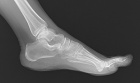

J.F. – 55 year old woman c/o left second toe pain for nearly three months after stubbing her toe.

Pain is dull, worse with activity. NSAIDs effective.

Zoom image: Radiological image Radiological image.